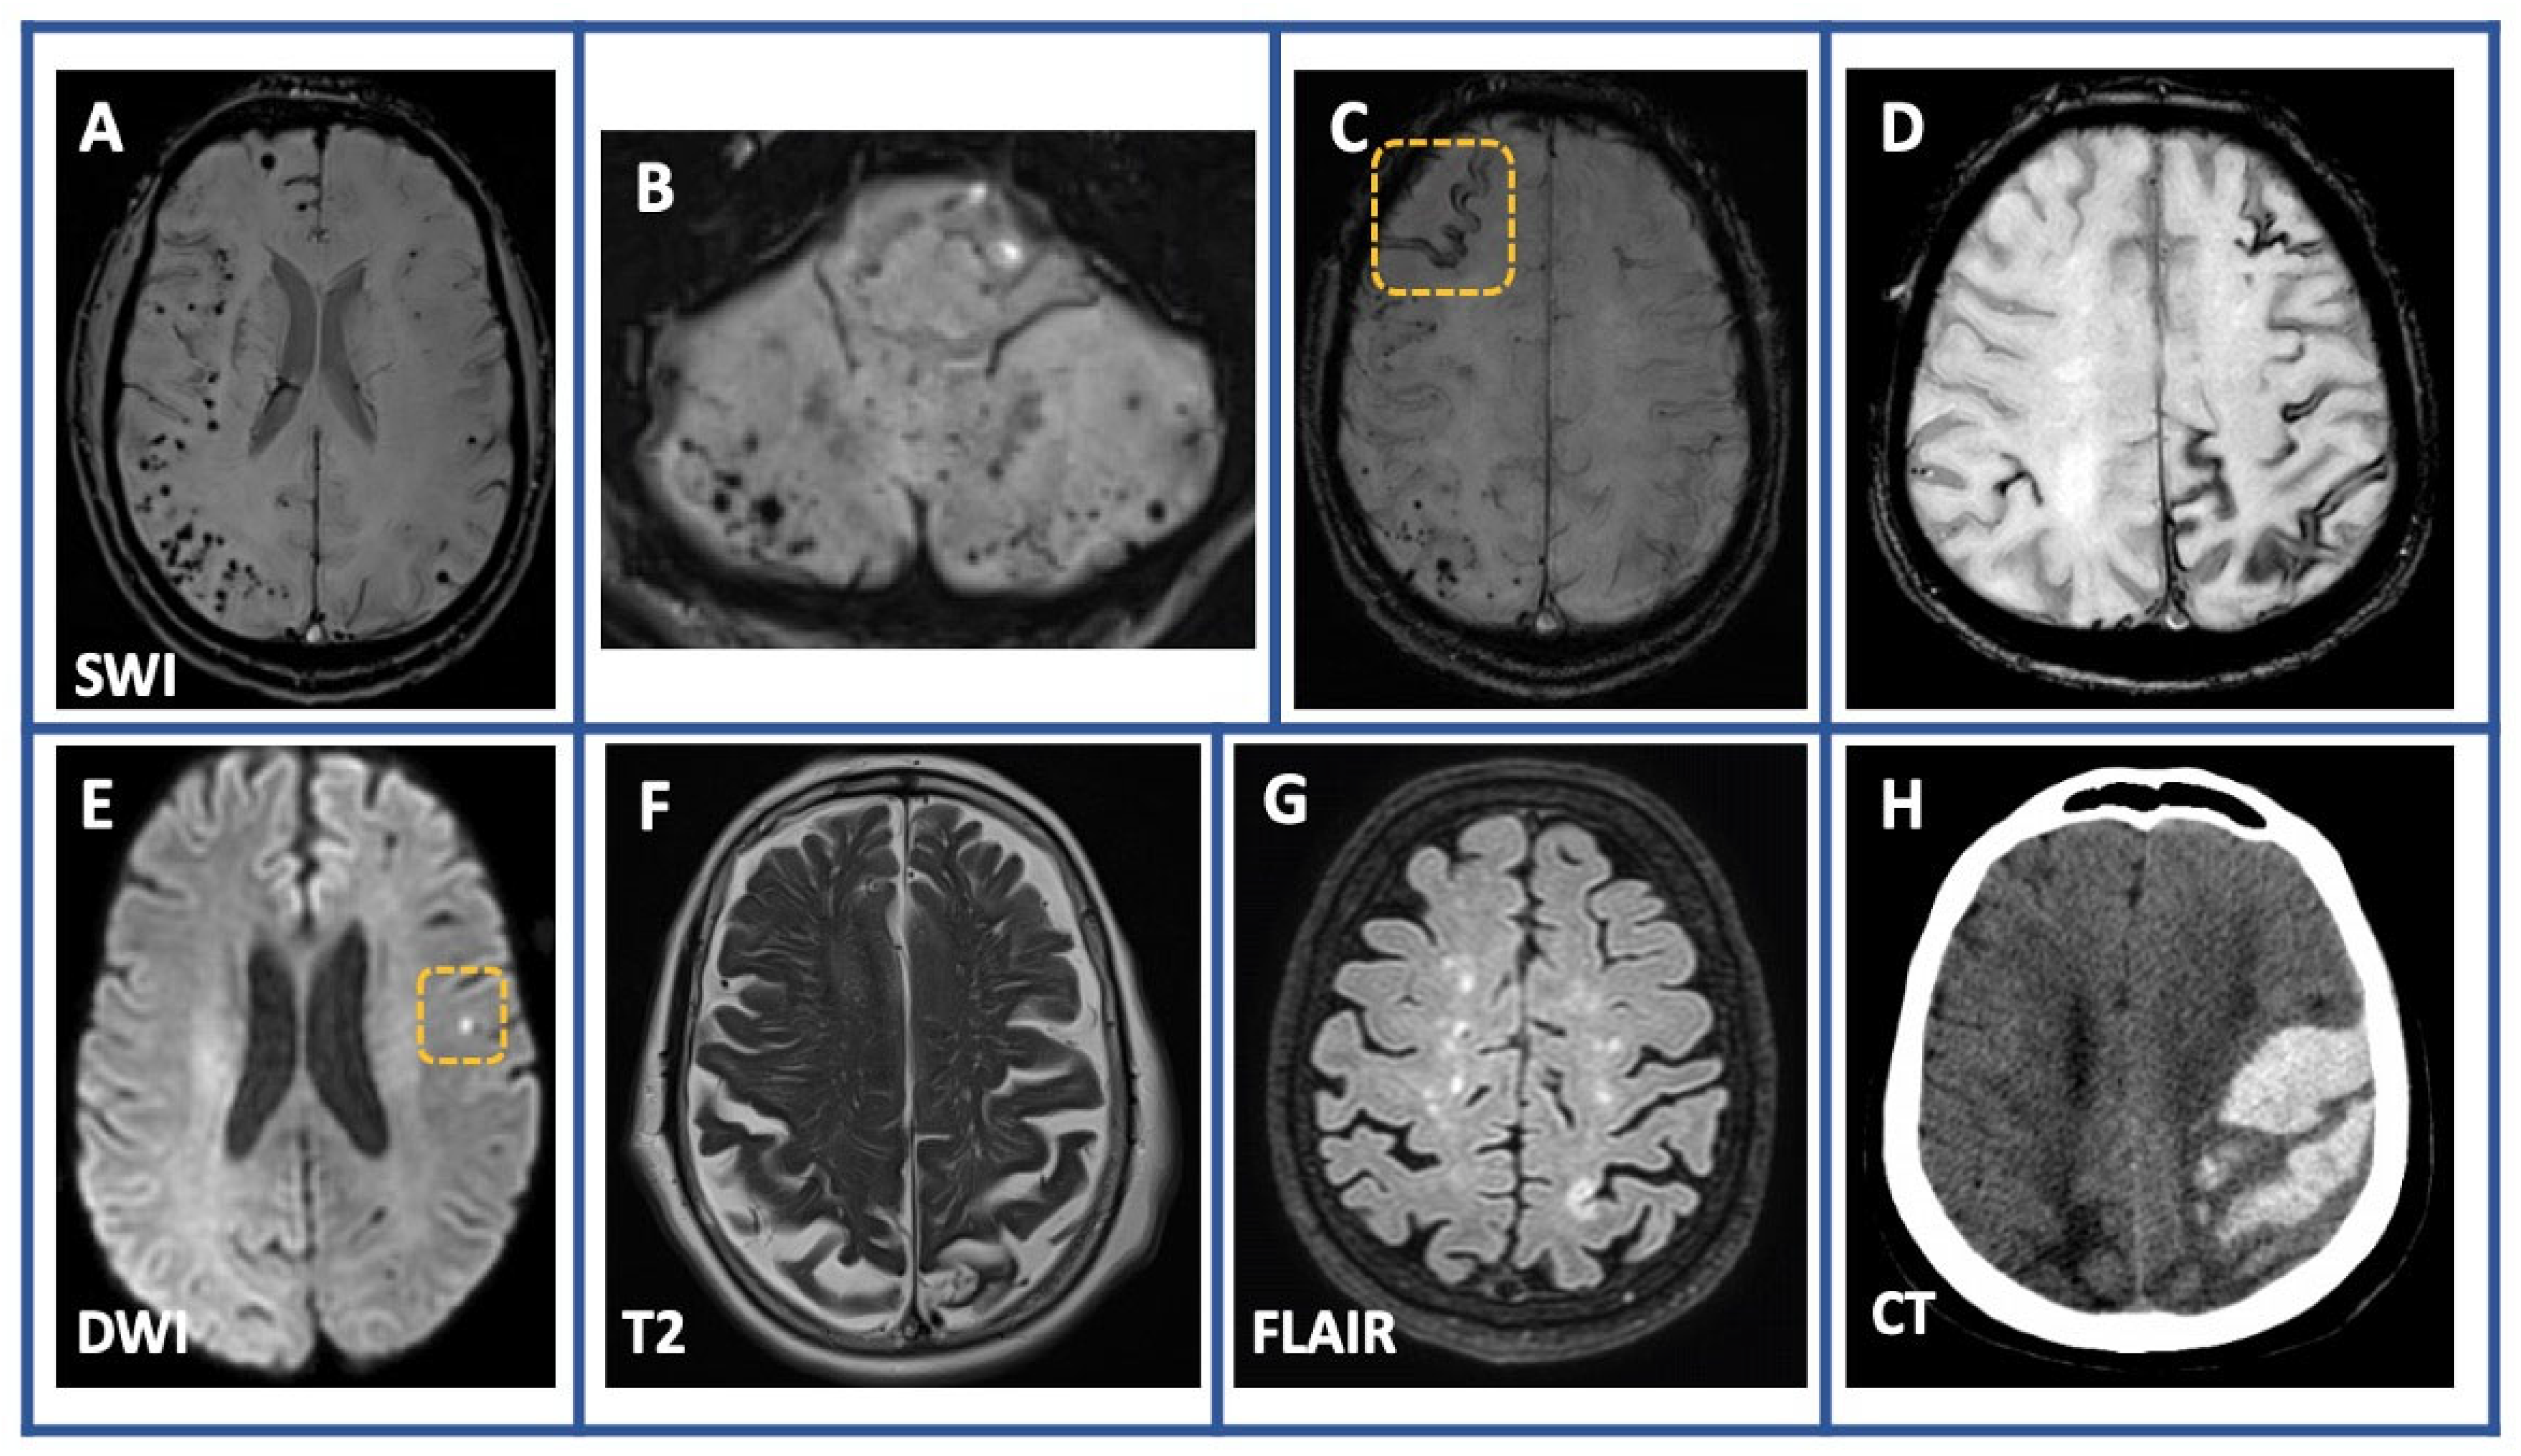

- Theodorou, A.; Chondrogianni, M.; Bakola, E.; Kaloudi, G.; Foska, A.; Michalakakou, S.; Melanis, K.; Paraskevas, G.P.; Tsivgoulis, G. Cortical Superficial Siderosis and Transient Focal Neurological Episode Preceding Lobar Hemorrhage in Cerebral Amyloid Angiopathy. Stroke 2023, 54, e48–e51. [Google Scholar] [CrossRef]